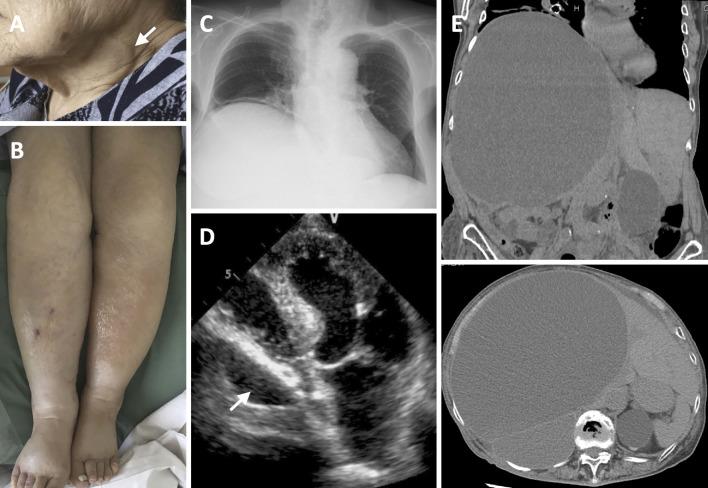

A Huge Liver Cyst Manifesting Dyspnea and Edema.